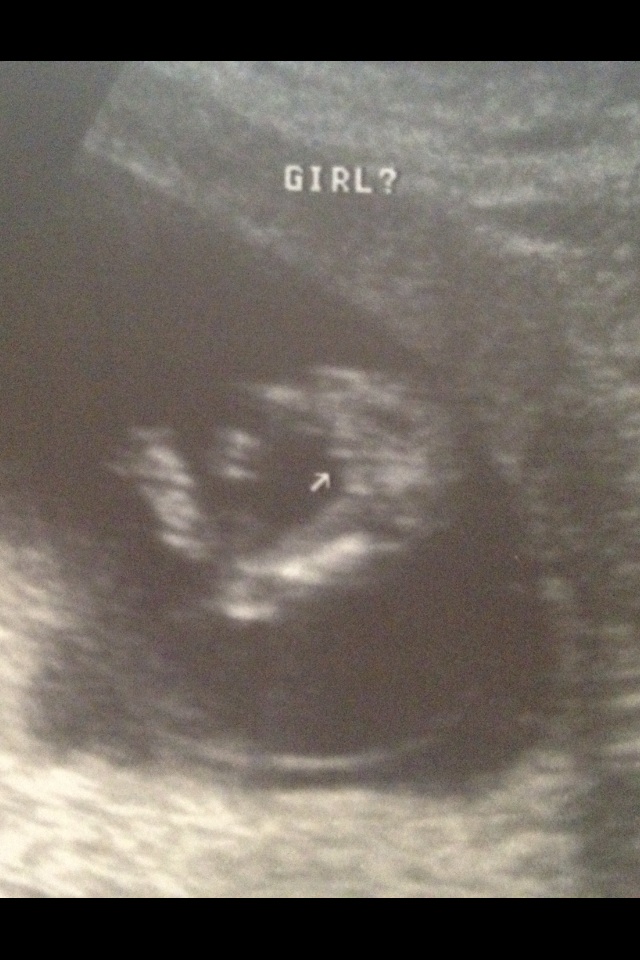

And here is the 13 week shot!!!!

Attachment 6376